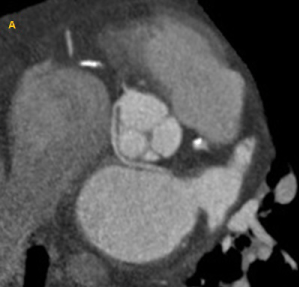

An anomalous origin of a coronary artery is a rare congenital condition that affects 1% of the population [1,2]. It is an anatomical variation in which a coronary artery arises from the opposite coronary sinus (Figure 1 and Figure 2). Some authors have described the anomalous origin of the right coronary artery (RCA) from the left coronary sinus (66% cases) as the most frequent coronary anomaly [2,3]. However, other case series have reported an anomalous origin of the circumflex (Cx) artery from the right coronary sinus with a retro-aortic course as the more prevalent [2].

Figure 1: Coronary computed tomography angiography example of anomalous origin of the coronary arteries: Left coronary artery originating from the right coronary sinus, with a retro-aortic course. View Figure 1

Figure 2: Coronary computed tomography angiography example of anomalous origin of the coronary arteries: Anomalous origin of the right coronary artery from the left coronary sinus, with an inter-arterial course. View Figure 2